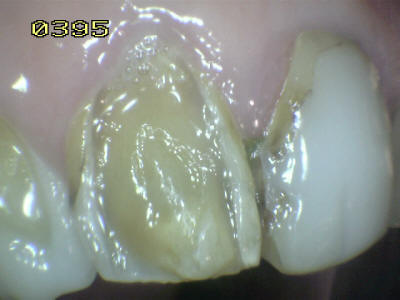

| Paciente de sexo femenino de 60 años de edad, que a la inspección

clínica se observa perdida de esmalte por erosión ácida en los dientes

antero-superiores. Durante el interrogatorio el paciente cuenta que

ingiere grandes cantidades de limón y naranjas naturales. Este habito

dietético ocasiona erosión ácida por el contenido de acido cítrico que

contienen dichas frutas. Note en las imágenes inferiores el deterioro

extenso del esmalte, que lleva en algunos sitios a la exposición de la

dentina. Como el proceso es gradual el paciente no tiene sintomatología

dolorosa al estímulo térmico.

Observe como se ha perdido

la estructura dental en 13, 12 y en 11 una carilla en

resina compuesta donde se ha deteriorado el borde cavo

superficial de la misma. En 23 el mismo patrón de

desmineralización dental |